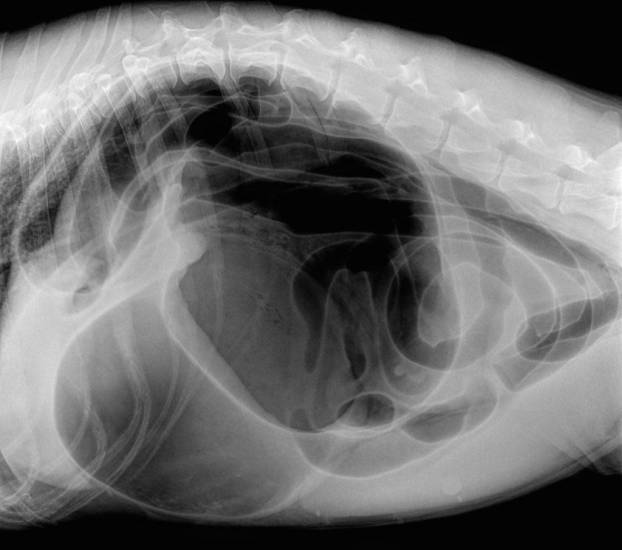

Устройство и механизм работы желудка

Желудок этого млекопитающего – это мешочек, который расположен таким образом, что самая широкая его часть находится спереди, соответственно сзади он сужен. С одной стороны желудка расположен вход пищевода, а с другой – выход в кишечник. Между ними находится «малая кривизна». Круглая мышечная складка при входе пищевода расположена таким образом, чтобы для проталкивания пищевых масс совершалось усилие, а употребленный вместе с едой воздух выталкивался.

Желудок в пустом состоянии расположен под левым ребром, но, наполняясь, он растягивается и доходит до нижней стенки живота. Именно эта способность влияет на возможность возникновения заворота кишок (перекручивание желудка и селезенки вокруг пищевода).

Началом заболевания становится процесс, при котором пищевой комок обрабатывается желудочным соком. Если корм содержит много углеводов, это приводит к усиленному газообразованию и увеличению объема желудка. Критическое вздутие вызывает перерастяжение стенок, что нарушает иннервацию и кровоснабжение, а также смещает орган в области, где расположена наиболее слабая связка, поддерживающая желудок в брюшной полости – в районе селезенки.

Под воздействием силы тяжести весь комплекс (сосуды, селезенка и желудок) начинает вращаться вокруг пищевода, что приводит к сжатию кровеносных и лимфатических сосудов. Ткани теряют питание, и развивается ишемия. Спустя 4 часа ткани начинают подвергаться некрозу (отмиранию), восстановление которых становится невозможным.